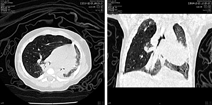

先天性大叶性肺气肿,现在又称婴儿肺叶过度充气(infantile lobar hyperinflation),是以肺叶进行性过度膨胀、对周围形成压迫为特征的先天性疾病,以左上叶最为多见,其次为右中叶、右上叶,通常单个肺叶受累,罕见多个肺叶或双侧受累。本病原因尚不清楚,部分是由于支气管壁软骨发育不良或缺乏,或支气管受到外源性压迫(肺动脉扩大、支气管源性囊肿、纵隔包块等),造成支气管在呼吸时形成单向阀门作用,吸气时进入气体不能完全被呼出,气体不断滞留所致。虽然肺泡扩张但肺泡壁结构正常,所以称为肺叶气肿不准确[2]。12%~14%的患儿合并心血管畸形。产前超声或MRI检查可较准确地诊断本病。出生后的临床表现取决于肺叶的膨胀程度和对纵隔或邻近肺组织的压迫程度,大多数在新生儿期即出现呼吸困难。胸片表现为受累肺叶过度膨胀,体积增大,透亮度增加,可见稀少纤细肺纹理。同时相邻的肺叶受压致体积缩小和密度增高,为压迫性肺不张。纵隔向健侧推移,可有纵隔疝形成。CT检查可更清晰地发现以上异常(图3)。影像学上容易与气胸和肺囊肿相混淆,但先天性大叶性肺气肿有正常的肺纹理。在年龄大的婴儿通常需要进行支气管镜检查,以除外支气管腔内阻塞,如黏液栓、肉芽和异物[5]。